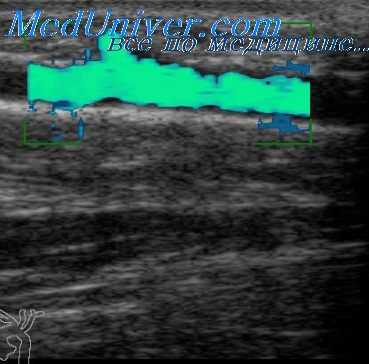

Оценка результатов поворотных проб предусматривает расчет индекса реактивности по формуле. Так, снижение пиковой систолической скорости кровотока в ПА при поворотах головы не более чем на 30% расценивают как отрицательную пробу, указывающую на отсутствие экстравазальной компрессии одной или обеих позвоночных артерий, с указанием направления ротации.

На рисунке показано выполнение поворотной пробы в режиме цветового дуплексного сканирования. Из рисунка видно, что при ротациях головы как в правую, так и в левую стороны, снижение пиковой систолической скорости кровотока в ПА не превышало 30% от исходного значения. Следовательно, делается вывод об отсутствии экстравазальной компрессии данной ПА при поворотах головы в обе стороны.